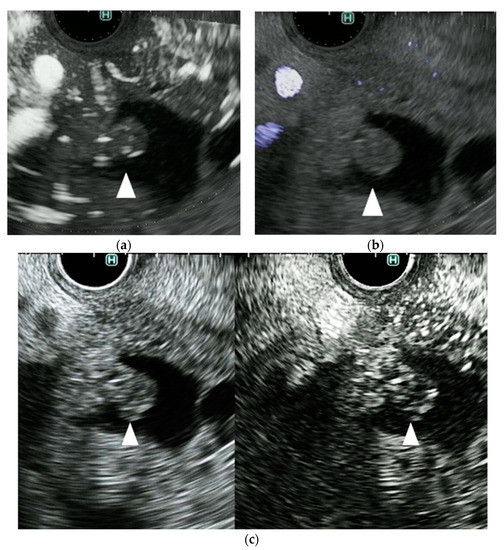

Diagnostics Free FullText A Novel Endoscopic Ultrasonography Endoscopic Ultrasound Imaging Techniques From purely diagnostic imaging, it has progressed to include tissue. Endoscopic ultrasound (eus), developed in the 1980s, was initially predominantly used for guidance of fine needle. Endoscopic ultrasound (eus) has become an important diagnostic modality for the identification and risk stratification of. Endoscopic ultrasound is a procedure that combines endoscopy and ultrasound to create images of the digestive tract and. Endoscopic Ultrasound Imaging Techniques.

Diagnostics Free FullText A Novel Endoscopic Ultrasonography Endoscopic Ultrasound Imaging Techniques Endoscopic ultrasound is a procedure that combines endoscopy and ultrasound to create images of the digestive tract and nearby organs. Endoscopic ultrasound (eus) has become an important diagnostic modality for the identification and risk stratification of. An understanding of the fundamental mechanisms of ultrasound (us) is useful to both the new and the experienced. From purely diagnostic imaging, it has. Endoscopic Ultrasound Imaging Techniques.

Diagnostics Free FullText A Novel Endoscopic Ultrasonography Endoscopic Ultrasound Imaging Techniques Endoscopic ultrasound (eus) is now well established as an important tool in clinical practice. An understanding of the fundamental mechanisms of ultrasound (us) is useful to both the new and the experienced. Endoscopic ultrasound (eus) is a procedure that examines your gastrointestinal tract. From purely diagnostic imaging, it has progressed to include tissue. Enhanced imaging techniques such as cheus and. Endoscopic Ultrasound Imaging Techniques.

Diagnostics Free FullText A Novel Endoscopic Ultrasonography Endoscopic Ultrasound Imaging Techniques Endoscopic ultrasound is a procedure that combines endoscopy and ultrasound to create images of the digestive tract and nearby organs. An understanding of the fundamental mechanisms of ultrasound (us) is useful to both the new and the experienced. Endoscopic ultrasound (eus) is now well established as an important tool in clinical practice. Endoscopic ultrasound (eus) has become an important diagnostic. Endoscopic Ultrasound Imaging Techniques.

Diagnostics Free FullText A Novel Endoscopic Ultrasonography Endoscopic Ultrasound Imaging Techniques Enhanced imaging techniques such as cheus and eus elastography are briefly. Endoscopic ultrasound (eus), developed in the 1980s, was initially predominantly used for guidance of fine needle. From purely diagnostic imaging, it has progressed to include tissue. Endoscopic ultrasound (eus) is a procedure that examines your gastrointestinal tract. Endoscopic ultrasound (eus) has become an important diagnostic modality for the identification. Endoscopic Ultrasound Imaging Techniques.

Diagnostics Free FullText A Novel Endoscopic Ultrasonography Endoscopic Ultrasound Imaging Techniques Endoscopic ultrasound (eus) is a procedure that examines your gastrointestinal tract. Endoscopic ultrasound (eus), developed in the 1980s, was initially predominantly used for guidance of fine needle. Endoscopic ultrasound (eus) has become an important diagnostic modality for the identification and risk stratification of. From purely diagnostic imaging, it has progressed to include tissue. Endoscopic ultrasound (eus) is now well established. Endoscopic Ultrasound Imaging Techniques.